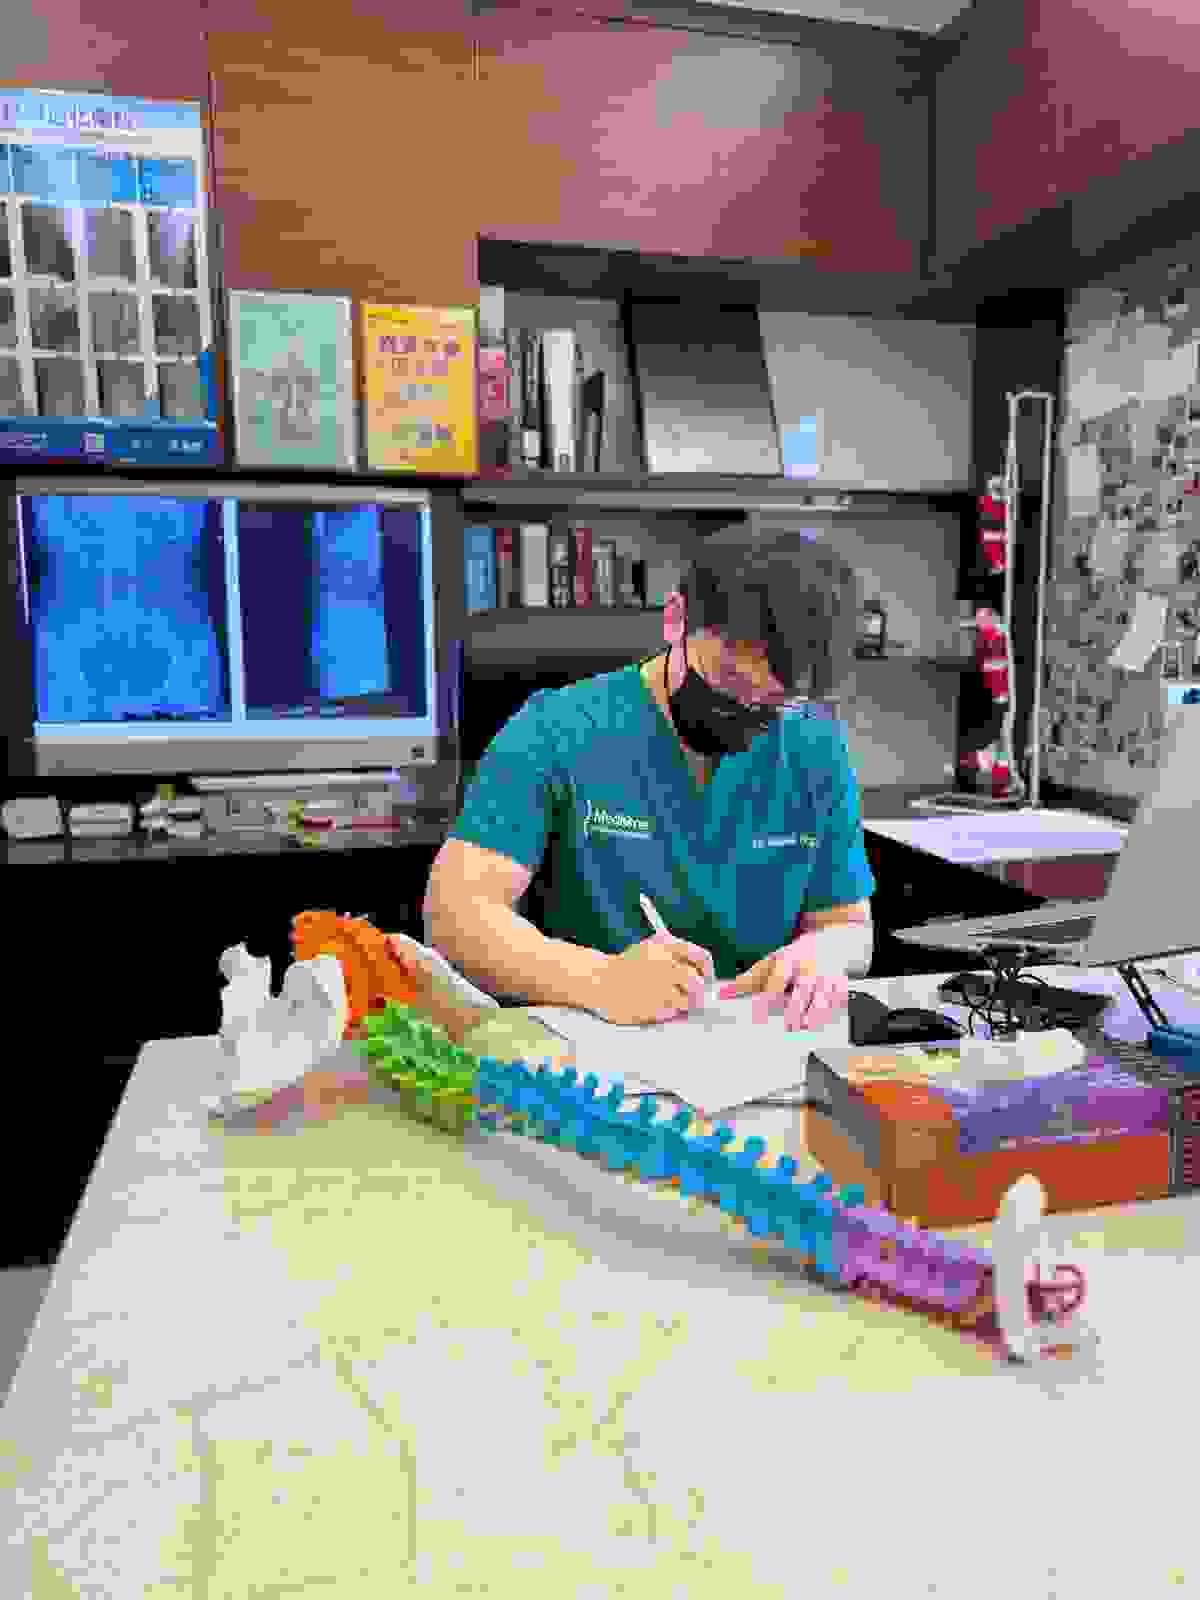

脊醫簡介

吳肇楠脊醫

脊骨神經科 (香港註冊編號 CC00203)

二十多年前,我還是個中五學生,一次打波跌倒,頸痛到連書包都背不起。西醫說「沒事,多休息」;中醫幫我針灸,痛楚只是暫時退卻。那年暑假,我媽媽帶我去見一位當時在紐西蘭還很罕見的「脊骨神經科醫生」(Doctor of Chiropractic)。

多年後,我遠赴紐西蘭讀脊骨神經科,拿了學位,又回到香港頂尖診所進修。每次當我把病人翻身、聽到那輕微的「咔」一聲,看見他們眼裡的驚喜與釋懷,我就想起當年那個中五男孩。